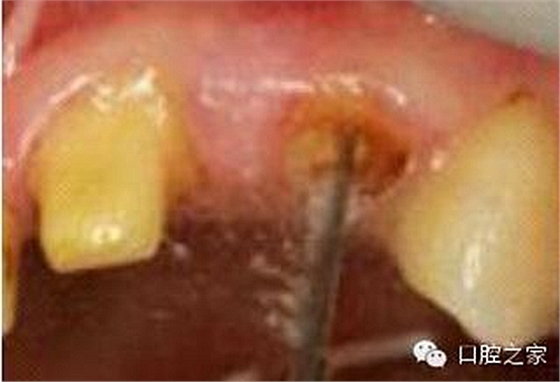

圖3:根管內(nèi)殘留物

圖4:超聲去除根管殘留物?! ?p>根管壁殘留物的存在直接影響著纖維樁的粘接和固位,是纖維樁脫落的主要原因之一。由于圓形的根管鉆和根管形態(tài)不完全一致,終鉆預(yù)備完成后大多情況下樁道側(cè)壁會有不同程度的牙膠和封閉劑等殘留物附著(圖 3)。因此,建議X線檢查根管預(yù)備情況,選用超聲潔牙機更換較細工作尖進入根管,徹底去除樁道根管壁上附著的殘留物(圖4)。使用根管銼去除殘留物時,很難清除干凈;禁止使用牙膠溶劑如丁克除、氯仿等有機溶劑去除殘留物,以免破壞根尖區(qū)牙膠的封閉,或有機溶劑粘附于根管壁形成蠟?zāi)ざ绊懻辰印?#pages##